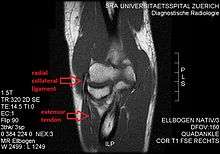

MRI of the elbow (T1 weighted) showing an unimpaired radial collateral ligament and extensor tendon.